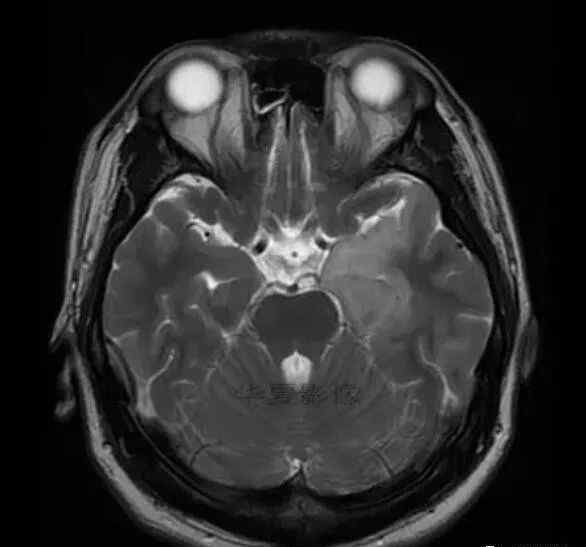

男,25岁,6天前意外感冒,现在发烧。他的体温超过39.0℃,他的呕吐物不是喷射状的。他的呕吐物是胃里的东西。

1.左侧颞叶、海马和岛叶T1WI信号低,T2WI信号高

2.病变没有明显的边界

3.占用效果不明显

4.豆状核不受影响